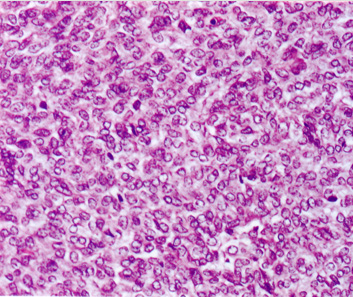

3. poorly differentiated type; 分化の低い類円形細胞肉腫でpericytomatous patternをとる。

biphasic type, monophasic typeは同じくらいの頻度で出現する。後者では免疫染色で上皮様分化をしめすこと, 特徴的な遺伝子異常を検出することが診断に必要となる。理論的にはmonophagic epithelial typeもあるが形態のみで診断は不可能。わずかな線維肉腫様成分をさがすことが診断にむすびつき, cytogenetic dataにより確診にいたる。